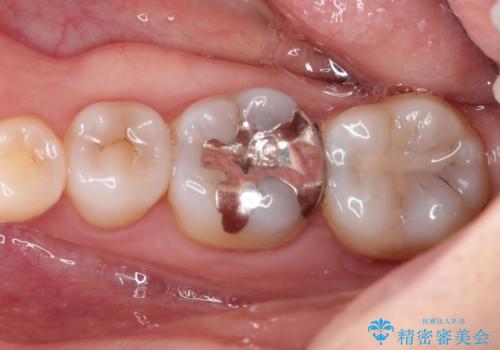

[ メタルフリー治療 ] 金属のない口腔内にしたい

![[ メタルフリー治療 ] 金属のない口腔内にしたいの症例 治療前](https://seimitsushinbi.jp/wp/wp-content/uploads/2021/09/2a134eb6522ae423858539412c8101be-500x350.jpg?v=1632299928)